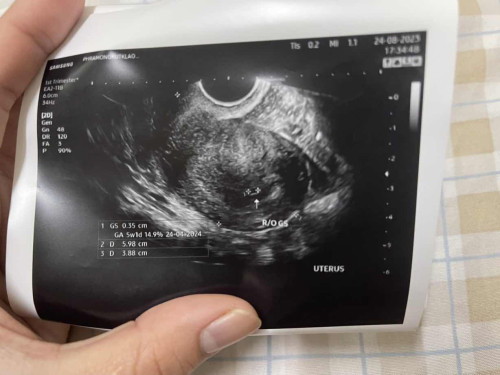

อ่านเพิ่มเติมรูปนี้ตอน 5W 3D ค่ะ (ดูจากมุมขวา)ยังไม่เจอเจ้าจิ๋วเลยค่ะ ของเรามาเจอหัวใจจริงๆช่วง 6-7 สัปดาห์ และเราตอนนั้นมีเลือดสีน้ำตาลอ่อน-เข้มออกมาค่ะ ไปโรงพยาบาลหมอบอกเป็นเลือดเก่าที่ค้างแต่ก็ได้มีการฉีดยากันแท้งมาให้ค่ะ หลังจากนั้นหมอแนะนำให้อย่าเดินเยอะ อย่ายกของหนัก พยายามนั่งหรือนอนเยอะๆค่ะ ตอนนี้น้องได้ 13 สัปดาห์แล้วค่ะ 😊

5 week เจอถุงตั้งครรภ์ ขนาด 5 มิล เองคะ 7 เกือบ 8 เจอน้องเป็นก้อนเต้นตุบๆๆๆๆ เพราะน้องมีหัวใจแล้ว

5สัปดาห์ค่ะ บ้านนี้เจอแต่ถุงตั้งครรภ์ แต่7สัปดาห์หมอนัดถึงจะเจอตัวน้องและเสียงหัวใจค่ะ